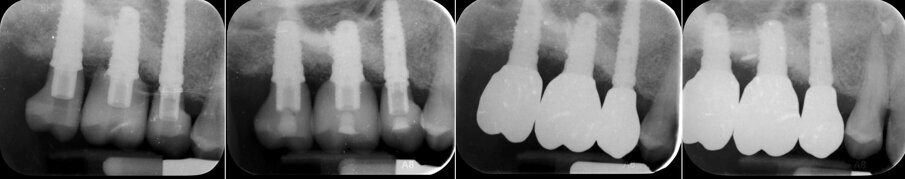

Dopo 3 mesi (T2), gli impianti sono stati esposti mediante un lembo spostato apicale per aumentare la quantità di tessuto cheratinizzato vestibolarmente agli impianti e riallineare la linea mucogengivale precedentemente spostata in direzione palatale; e sono state applicate viti di guarigione svasate per favorire una corretta guarigione trans-mucosa. Dopo 1 mese (T3), sono state eseguite corone singole in ceramica, per il primo carico funzionale e la finalizzazione provvisoria del caso, in attesa della maturazione ossea completa (Fig. 34). Dopo 6 mesi (T4), le corone sono state sostituite con corone in zirconio, per il carico funzionale e la finalizzazione definitiva degli impianti (Figg. 36-38). I controlli clinici e radiografici al primo carico funzionale, a 6 mesi, a 12 mesi, e a 24 mesi, mostrano la salute dei tessuti peri-implantari e il mantenimento dei livelli ossei peri-implantari (Fig. 39).